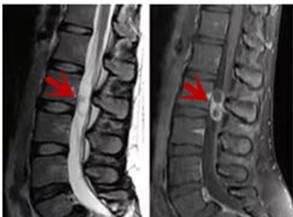

利器三:MRI(核磁共振)

MRI利于磁场和射频脉冲使体内的氢原子核发生磁共振现象而产生的图像,对软组织的分辨率很高,对于脊髓、椎间盘、神经、血管、韧带、骨髓、腰部肌肉及周围软组织有很好的显示效果,可以清晰的显示腰椎间盘突出对硬膜囊、神经根压迫程度,以及骨折是陈旧还是新鲜,同时在脊髓病变(如脊髓损伤、髓内出血或肿瘤)、椎管内脓肿/血肿、椎旁肌肉软组织病变等方面也具有优势,但是检查时间较长,部分患者可能因体内金属植入物(如心脏起搏器、人工耳蜗等)而无法进行检查。

箭头提示腰椎管内肿瘤